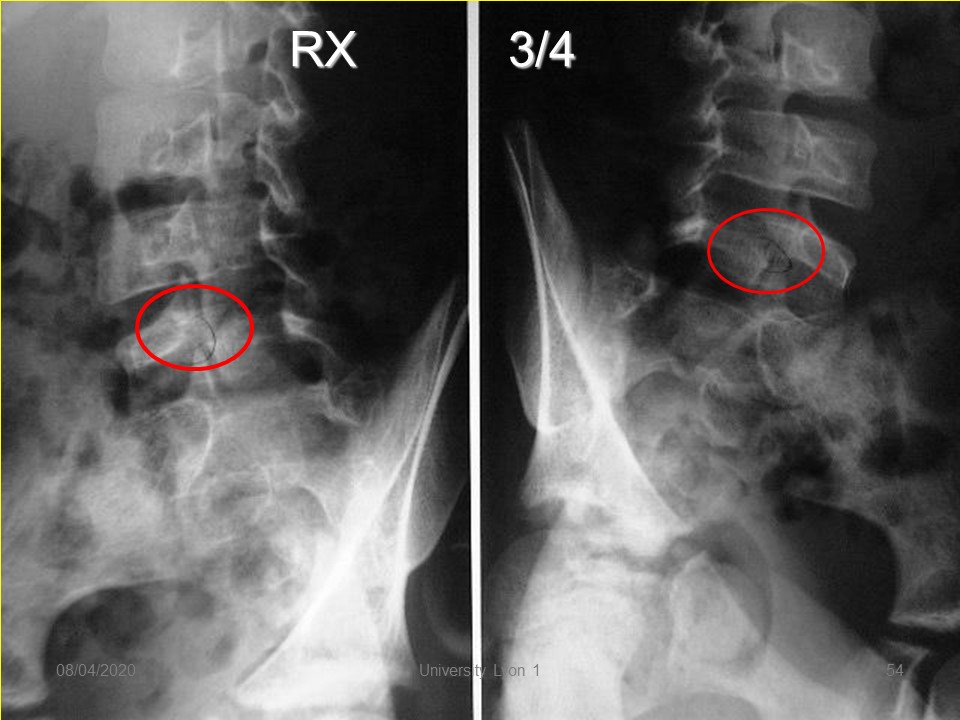

Radiologically, the image of ¾ makes it possible to better visualize pars interarticularis when the lysis is of the poorly visible crack type.

The radiography of ¾ makes it possible to better visualize the pars interarticularis when the lysis is of crack type poorly visible.